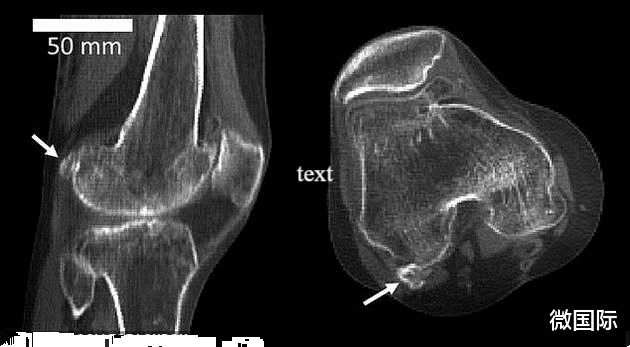

其实这个东西叫做法贝骨 , 这是一种人体内极为罕见的骨头 , 世界上只有少数人体内拥有这种骨头 。 因为人类在进化的过程中 , 早已经将其给进化掉了 。

据了解 , 这骨头位于膝盖处 , 一般在哺乳动物的身上比较常见 , 尤其是一些灵长类的动物 , 比如说像猩猩和猴子 。 但是人类的身上 , 现在基本上是看不到的 , 因为用进废退的道理 , 相信大家都懂 。

根据数据显示 , 其实最早发现法贝骨是在1875年 。 当时拥有法贝骨的人的数量已经占据了人类总数量的百分之11 , 在2018年已经到达了40% 。 我们从数据来分析 , 其实这个法贝骨拥有的人数 , 其实在逐年上升的 。

至于为什么会重新出现 , 其实根据科学家的说法 , 这个是与人类的活动有关的 。 而这块骨头的出现 , 可以增强膝关节的能力抵御身体给膝盖带来的压力 , 避免膝盖之间的摩擦和劳损 。 也就是说 , 可能是因为人类的运动量增加 , 所以这块骨头重新出现 。 另外一种说法 , 就是人类的生活水平提高 , 物质水平的提高 , 导致这块骨头的出现 , 至于是退化还是进化 , 现在科学界还存在于一定的争议 。